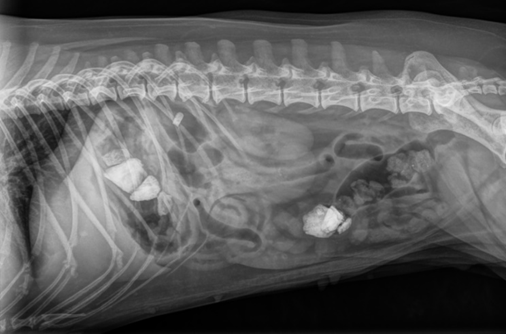

Seuraavaksi Riisi siirtyikin röntgenpöydälle, jolloin syy mahakivulle sekä oksentamiselle paljastui.

Riisin mahassa todettiin röntgentiiviitä kappaleita, tässä tapauksessa kiviä. Osa kivistä oli vielä mahalaukussa, mutta osa oli edennyt jo pidemmälle paksusuoleen asti.